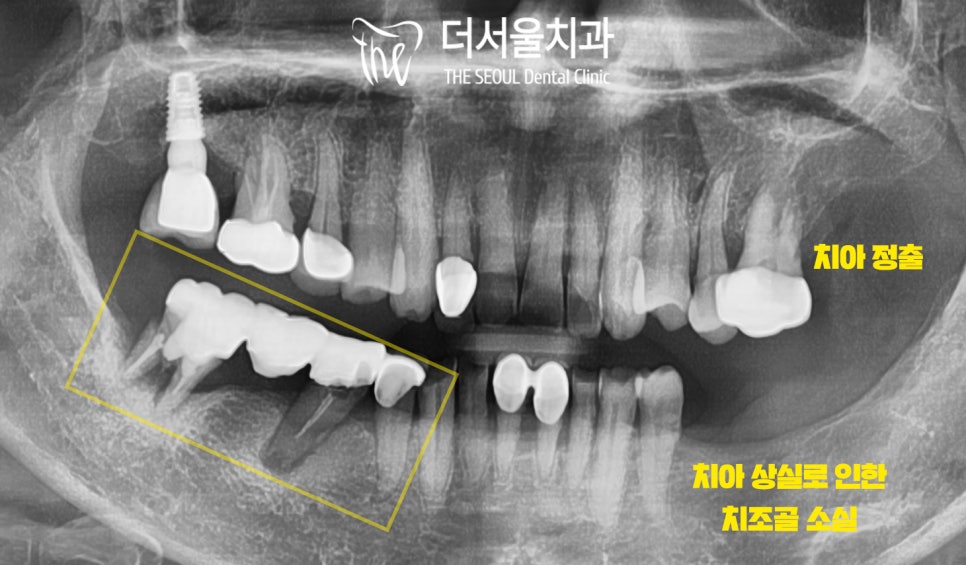

엑스레이 촬영을 통해 좀 더 자세히 살펴보니

빠져버린 치아 말고도 여러 문제들이 관찰되었습니다.

1) 곳곳에 심한 골소실

2) 대합치 정출

3) 심한 동요

전체적으로 구강 상태가 좋은 편은 아니었죠.